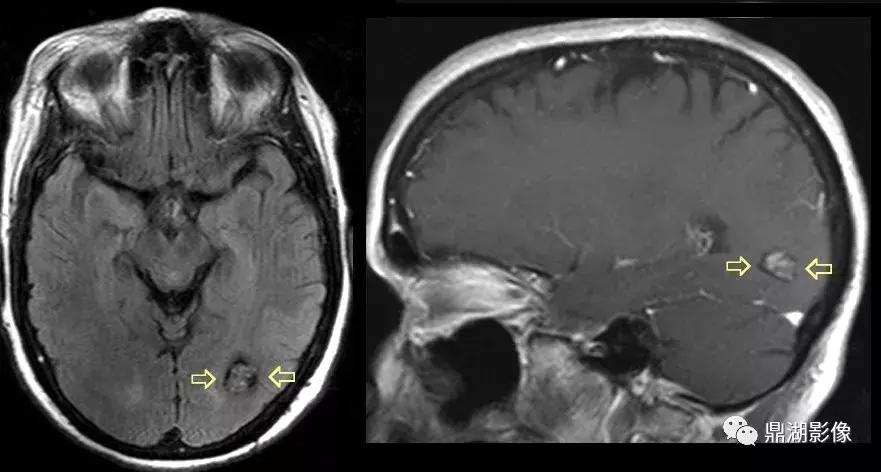

3.MRI表现:T1W呈稍低信号或低信号,有出血时可见不均匀高信号;T2WI可呈高信号,周边可见特征性环状低信号,为含铁血黄素沉着所致。一般不需要强化扫描。MR是最佳的影像检查方法。

补充:其中富含血液的血窦T1WI上呈明显的低信号,T2WI为高信号。病灶中心出血后,含铁血黄素沉积及瘤体钙化及增生的胶质使病灶的T2WI呈混杂信号,病灶周边纤维变性的脑组织形成的假包膜T2WI则显示为环形低信号。磁敏感加权成像技术是以T2*梯度回波序列为基础,利用不同组织间的磁敏感性差异而产生图像对比增强的MR成像方法,可同时获得 磁距 图像和相位图像。由于磁敏感物质可造成局部磁场不均匀性,引起质子失相位,产生顺磁性,在SWI序列上表现为低信号,所以SWI序列对磁敏感物质极为敏感,脑内海绵状血管瘤在SWI像上表现为明显低信号。